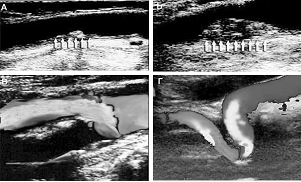

Рис. 2. УЗДГ сонных артерий. Стенозы (вверху) и извитости (кинкинг) сонных артерий (внизу).

УЗДГ во всем мире является «золотым стандартом» скрининга атеросклероза, т.е. врачи используют этот метод при массовом обследовании людей для выявления лиц с этой болезнью. Он является доступным, менее затратным, чем другие методы исследования. УЗДГ выявляет изменение объема кровотока в сосуде, степень сужения данного сосуда, по определенным признакам может указать, что причиной сужения сосуда является атеросклеротическая бляшка в его стенке (рис. 2). Если артерия сужена на 50 процентов и более, для более детальной оценки состояния сосуда врач может порекомендовать пациенту ангиографию – рентгеноконтрастное исследование кровеносных сосудов.

Рис. 2. УЗДГ сонных артерий. Стенозы (вверху) и извитости (кинкинг) сонных артерий (внизу).УЗДГ во всем мире является «золотым стандартом» скрининга атеросклероза, т.е. врачи используют этот метод при массовом обследовании людей для выявления лиц с этой болезнью. Он является доступным, менее затратным, чем другие методы исследования. УЗДГ выявляет изменение объема кровотока в сосуде, степень сужения данного сосуда, по определенным признакам может указать, что причиной сужения сосуда является атеросклеротическая бляшка в его стенке (рис. 2). Если артерия сужена на 50 процентов и более, для более детальной оценки состояния сосуда врач может порекомендовать пациенту ангиографию – рентгеноконтрастное исследование кровеносных сосудов.